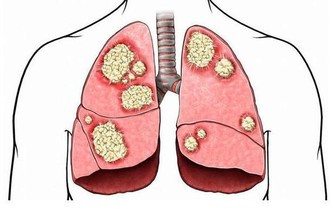

我們都知道這個部位有很多的褶皺,最容易殘存一些臟東西,比如糞便,長時間的不清潔,這其中的細菌會在肛門處肆意的繁衍,最終形成痔瘡,出現便血,並且會有明顯的疼痛感,嚴重的情況可能會出現肛門脫出的情況。

就像文中的小剛一樣,這是一種急性感染類的疾病,主要的病因是就細菌引起的,通常會出現在20歲到40歲的男性身上,患病後肛門的部位會感覺到疼痛和灼燒感,並且會有明顯的腫脹。嚴重的情況還會出現肛周的分泌物。甚至肛門周圍皮膚潰爛。